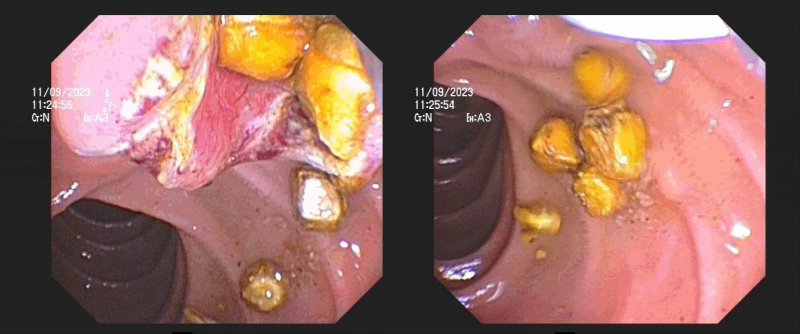

Quá trình nội soi chụp đường mật tụy phát hiện ống mật chủ giãn, đường kính chỗ giãn lớn nhất khoảng 12mm, trong lòng có rất nhiều sỏi cản quang. Ekip can thiệp nội soi của BS CKI Nguyễn Quảng Đại – Trưởng Khoa Nội tiêu hóa, tiến hành cắt cơ oddi, dùng bóng Balloon kéo sỏi tầm soát từ ống gan chung xuống tá tràng nhiều lần, lấy được khoảng hơn 20 viên sỏi, kích thước mỗi viên sỏi khoảng 5-10mm. Ca can thiệp thành công trong khoảng 45 phút. Chỉ sau ít phút, bệnh nhân tỉnh táo trở lại, được chuyển về bệnh phòng điều trị. Sau 24h, bệnh nhân hết đau, ăn uống và sinh hoạt bình thường.

Hình ảnh sỏi trong lòng ống mật chủ của bệnh nhân trên màn hình nội soi